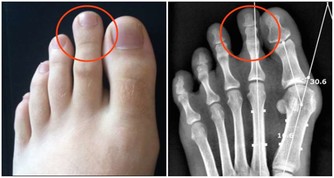

跟癌症、心腦血管疾病相比,關節炎似乎算不上多麼致命的疾患,然而它發作時的痛苦程度,讓所有患者一想起來就心有餘悸。想想手部、手腕、腳部關節疼痛、腫脹、僵硬的滋味吧,你一定不會喜歡的。

可是,如果已經罹患關節炎了,該怎麼辦呢?畢竟,患關節炎的人不在少數。這時候,我們需要做的就是減少關節炎發作的頻率,這不是不可能的。